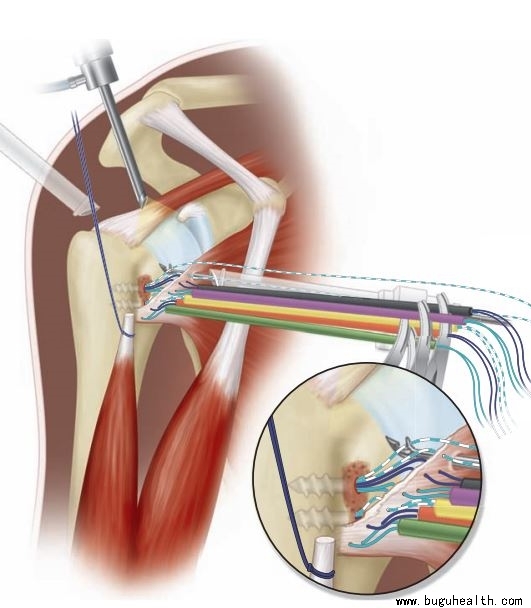

- 布骨医学科普:浅谈肩胛动力功能障碍----肩胛运动失衡 布骨康复医疗中心 ,2022-03-23

- 肩是体育运动和日常生活中完成各项运动的重要环节,特别是在肩上举过顶项目的运动员中,肩部损伤发生率最高。比如投掷类的标枪、铁饼、排球、网球、乒乓球等项目运动员,都属于上举过顶运动项目,当然也就意味着运动员肩部疼痛和损伤的发生率很高。那么,肩关节疼痛我们也就自然而然引出这么个概念“肩胛动力功能障碍”,如.....